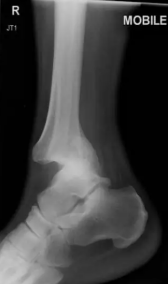

medial malleoulus

distal tibula

lateral malleolus

distal fibula

happens in ankle fracture/dislocation

separation of tibia and fibula from talus

ankle fracture / dislocation mechanism (2)

foot forced inward/outward, foot planted and lower leg forcibly rotated

signs/symptoms of ankle fracture/dislocation

severe pain/deformity, open fracture, no weight bearing

ankle fracture/dislocation treatment

immobilize, apply light pressure, ice + elevate if no open wound